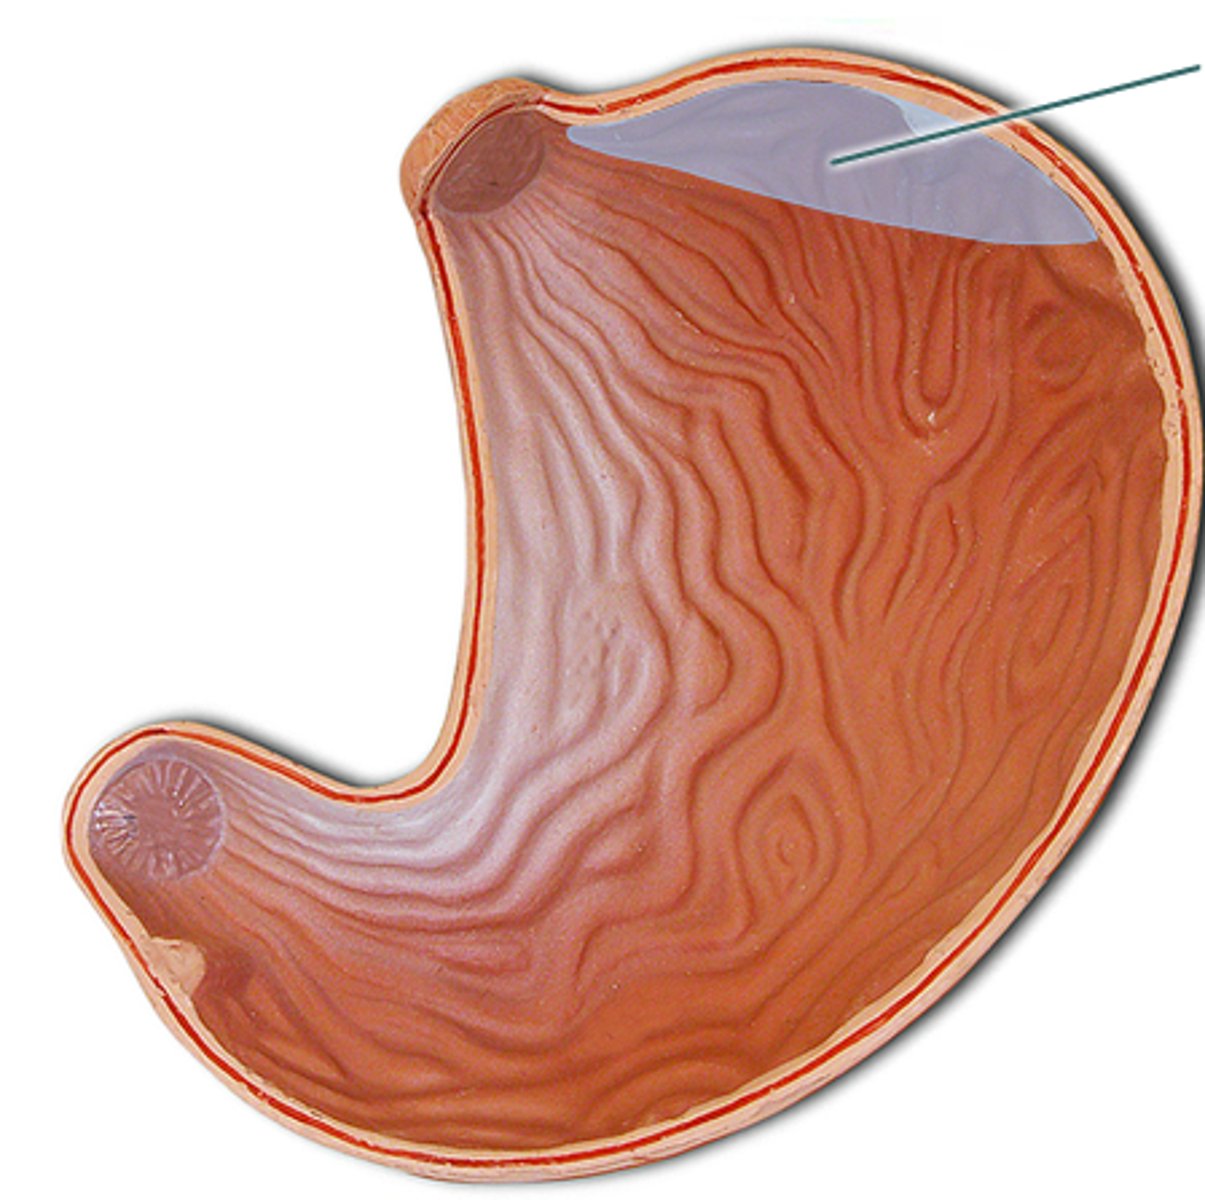

stomach

fundus

cardia

body

lesser curvature

greater curvature

cardiac sphincter / lower esophageal sphincter

pylorus

pyloric sphincter

rugae